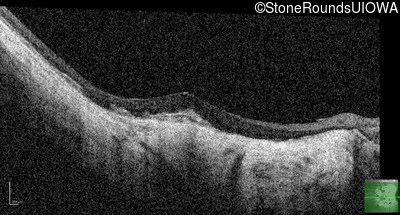

Optical Coherence Tomography - Left - 20/25 -2

Exemplar / OCT Stack